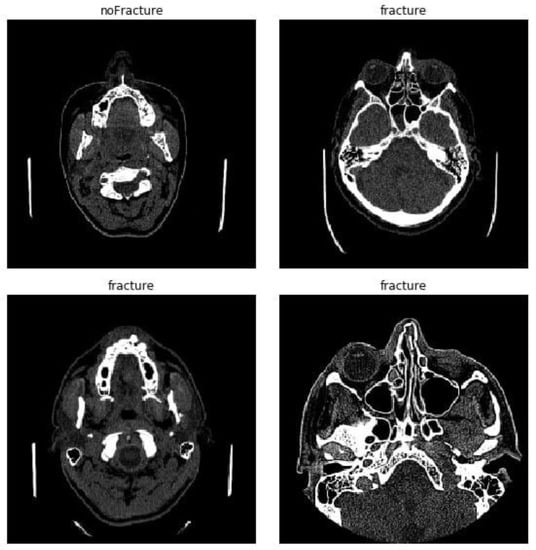

2.1. Dataset